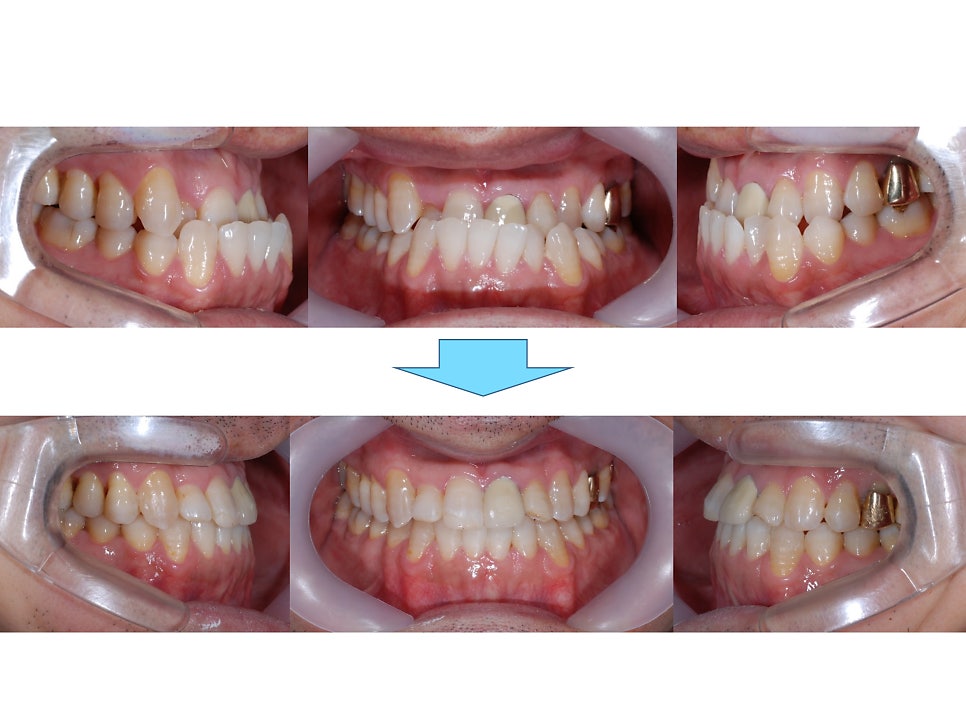

ºñ¼ö¼ú ÁÖ°ÆÅÎ ÀüÈÄ ±³ÇÕÀÔ´Ï´Ù.

¾Æ·¡ÅÎÀÌ ¸¹ÀÌ ¾ÕÀ¸·Î ³ª¿ÍÀÖ¾ú´Âµ¥

¾ç¾Ç¼ö¼úÀÌ ¾Æ´Ï¶ó

±³Á¤Ä¡·á ¸¸À¸·Î

±³ÇÕÀÌ Àß °³¼±µÈ °ÍÀ»

º¼ ¼ö ÀÖ½À´Ï´Ù.

ºñ¼ö¼ú ÁÖ°ÆÅÎ ±³Á¤Ä¡·á ÀüÈÄÀÔ´Ï´Ù.

Á¤»ó±³ÇÕÀ¸·Î

°³¼±ÀÌ Àß µÇ¾ú°í

ºñ¼ö¼ú ÁÖ°ÆÅÎ ±³Á¤Ä¡·á ÈÄ

2³âÀÌ °æ°ú µÇ¾îµµ

ÁÁÀº ±³ÇÕÀ» Àß À¯ÁöÇϰí À־

³Ê¹« ´ÙÇàÀÌ¿´½À´Ï´Ù.

¿À·§µ¿¾È ÁÁÀº ±³ÇÕÀÌ Àß À¯ÁöµÈ´Ù´Â °ÍÀº

ºñ¼ö¼ú ÁÖ°ÆÅÎ ±³Á¤Ä¡·á·Î

°³¼±µÈ ±³ÇÕ¿¡ ¸ÂÃç¼­

¹Ù¸¥ ÀúÀÛ, ¿¬ÇÏ, È£Èí µî

Ä¡¾Æ¸¦ µÑ·¯½Ñ ¿¬Á¶Á÷ÀÇ

¾ÈÂʰú ¹Ù±ùÂÊÀÇ ±ÕÇüÀÌ Àß ÀÌ·ïÁ® Àֱ⠶§¹®¿¡

½Ã°£ÀÌ Áö³ªµµ

±³ÇÕÀÌ Èçµé¸®Áö ¾Ê°í

Àß À¯ÁöµÉ ¼ö ÀÖ´ä´Ï´Ù.